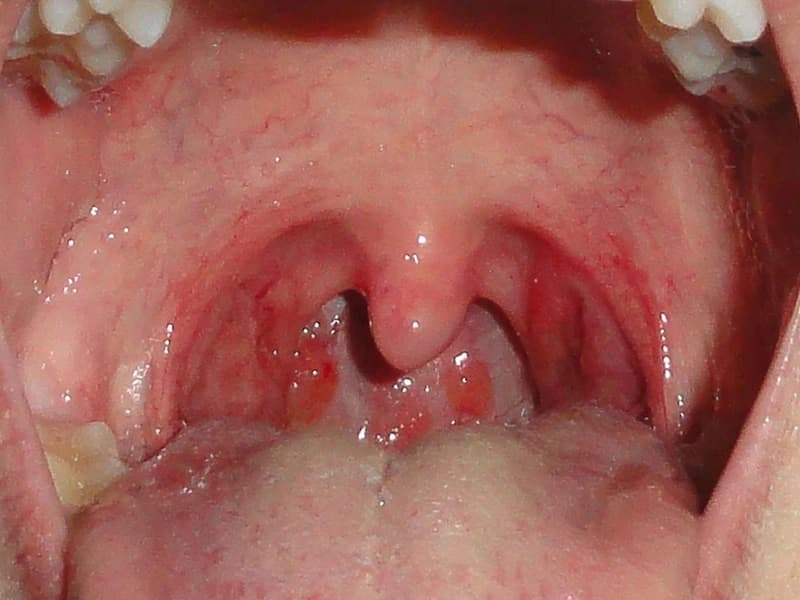

Viêm xoang và viêm Amidan: Những bệnh lý này thường gây ra sự tích tụ của dịch mủ trong khoang mũi và họng, từ đó vi khuẩn có thể phát triển mạnh mẽ và gây ra hôi miệng. Viêm amidan có thể dẫn đến việc hình thành các cục bã đậu (tonsilloliths), gây ra mùi hôi nặng nề.